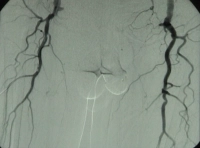

DAOP perna direita grau IV de Fontaine, perna esquerda grau III com:

- Arteriosclerose de alto grau da aorta terminal e de ambas as artérias ilíacas

- Oclusão estendida de ambas as artérias femorais superficiais

- Oclusão parcial das artérias infrapoplíteas em ambas as pernas

DSA pré-operatória: